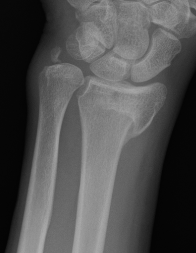

Xray

Bilateral xrays

PA film in neutral

- wrist neutral

- elbow & shoulder at 90°

Malunion

| Radial shortening | Radial inclination | Positive ulna variance |

| Dorsal tilt > 15 degrees | Volar tilt > 10 degrees | Articular step > 3 mm |